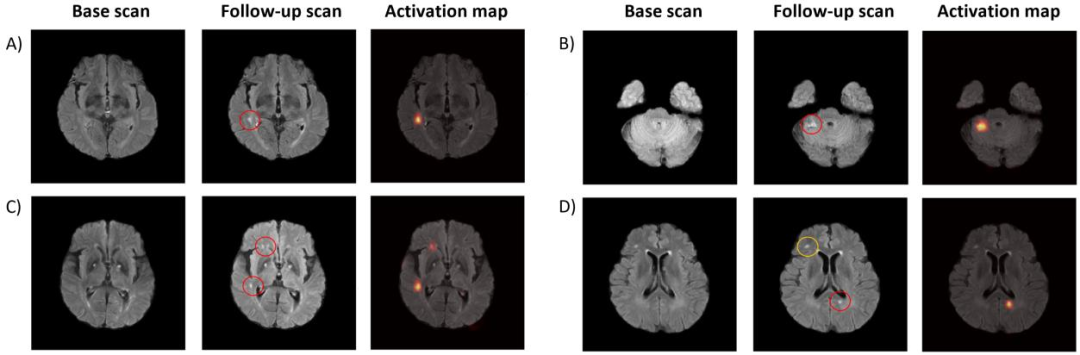

患者级内部AUC为0.861(95%CI 0.809–0.912),外部AUC为0.892(95%CI 0.862–0.923);Grad-CAM热力图所高亮区域与影像确认的新发梗死灶高度一致,证实模型习得了具有临床意义的局灶特征而非噪声。(Fig. 2)

图2.模型面板A-D确定的新发展梗死的代表性案例显示了新发展梗死(后续FLAIR扫描上的红色圆圈)通过Grad-CAM激活图正确定位的示例,突出显示的区域对应于真实的病变部位。面板D显示了一个真正的新梗死(红色圆圈)和预先存在的信号变化(黄色圆圈)的案例。该模型选择性地激活了新病变,同时适当忽略了预先存在的区域,表明病变检测具有稳健的特异性。